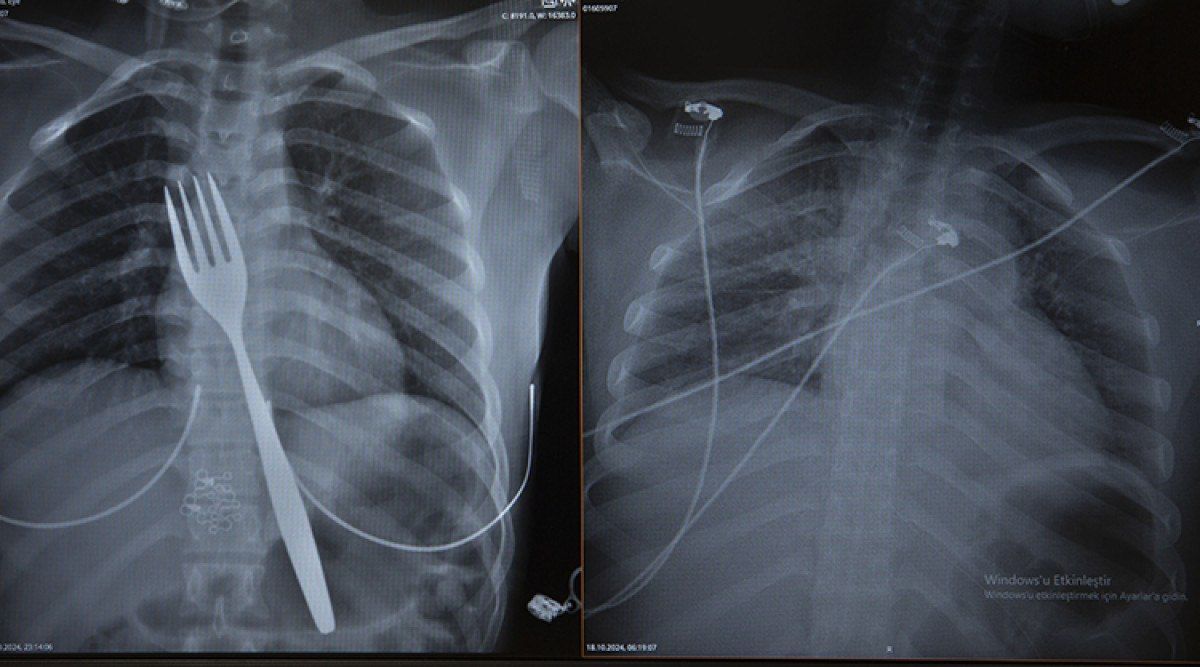

Burada röntgeni çekilen hastanın yemek borusunda 18 santimlik çatal olduğu tespit edildi.

Uzmanlar endoskopi yaparak çatalı ağızdan çıkarmayı denedi. Fakat yemek ve soluk borusuna zarar verme ihtimalinden dolayı midenin kesilerek çatalın çıkarılmasına karar verildi.

Vakayı ilk duyduğunda şaşırdığını anlatan Edizsoy, “Büyük bir çatalın tamamen yutulması şeklinde ortaya çıkan bu vakayı ilk duyduğumda doğru olmadığını düşündüm. Hasta 18 yaşında ve yabancı uyrukluydu. Türkçesi biraz zayıf olduğu için belki de yanlış anlaşılmalar olabileceğini düşündük. Ama hastanın filmini çektiğimizde gerçekten bir çatalın yemek borusunda olduğunu gördük.” dedi.

Biz en çok bu yüzden tedirgin olduk. Ama ciddi bir yaralanma olmadığını da yapılan endoskopiyle gördük. Endoskopi ile çıkarılamadı çünkü oldukça büyüktü ve endoskopik aletler için uygun değildi. Bu büyük bir yemek çatalı olduğu için kendi ağırlığı da var. Bir çivi gibi, iğne gibi tutulup çekilemiyor. Bundan dolayı karında yapılan kesi ile mideye ulaşıp midenin içinden bunu çıkarmak şeklinde bir strateji izledik. Yaptığımız bu ameliyatla da bu çatalı oradan çıkarabildik.